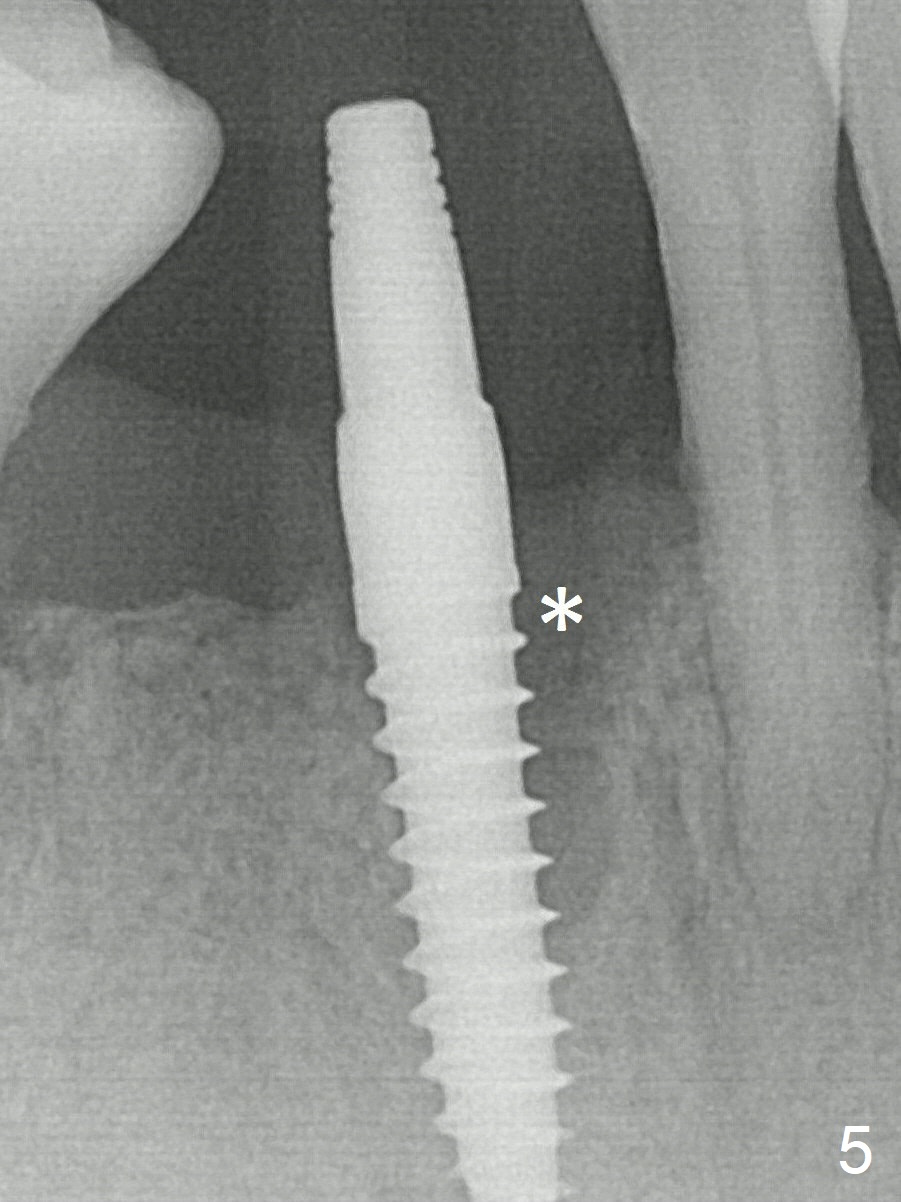

A 3x16(2) mm 1-piece implant is being placed as distal as possible (Fig.5 with 45 Ncm) with the mesial gap (*). The latter is filled with bone graft (Fig.6 *). The implant threads are not exposed 3 months 1 week postop (Fig.12).